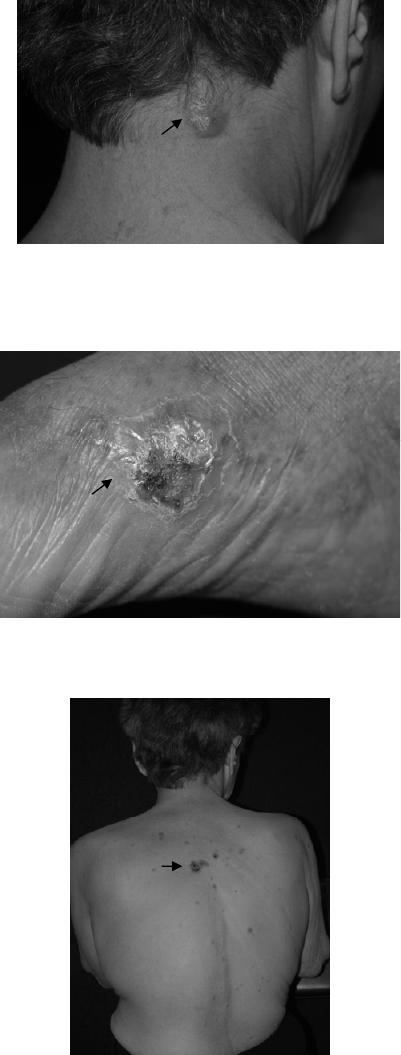

Figura 9: Raro caso de CBM com lesões planas faciais disseminadas...................................24

Figura 10: Caso incomum de CBM com lesões elevadas e disseminadas no membro

inferior e carcinoma associado (seta).....................................................................25

Figura 11: Caso raro de CBM com lesões elevadas disseminadas recrudescente após

várias terapias..........................................................................................................25

Figura 12: Exemplo de lesão plana (seta)................................................................................25

Figura 13: Exemplos de Lesões elevadas (setas)....................................................................25

Figura 14: Extensa lesão plana (limitada pelas setas).............................................................26

Figura 15: Detalhe de lesão plana (seta)..................................................................................26

Figura 9: Raro caso de CBM com lesões planas faciais disseminadas.

Figura 10: Caso incomum de CBM com lesões Figura 11: Caso raro de CBM com lesões

elevadas e disseminadas no membro inferior elevadas disseminadas recrudescente

e carcinoma associado (seta). após várias terapias.

Figura 12: Exemplo de lesão plana (seta).

Figura 13: Exemplos de Lesões elevadas (setas).

Figura 14: Extensa lesão plana (limitada pelas setas). Figura 15: Detalhe de lesão plana (seta).

Fonte: Fototeca do Serviço de Dermatologia do CHSCPA.